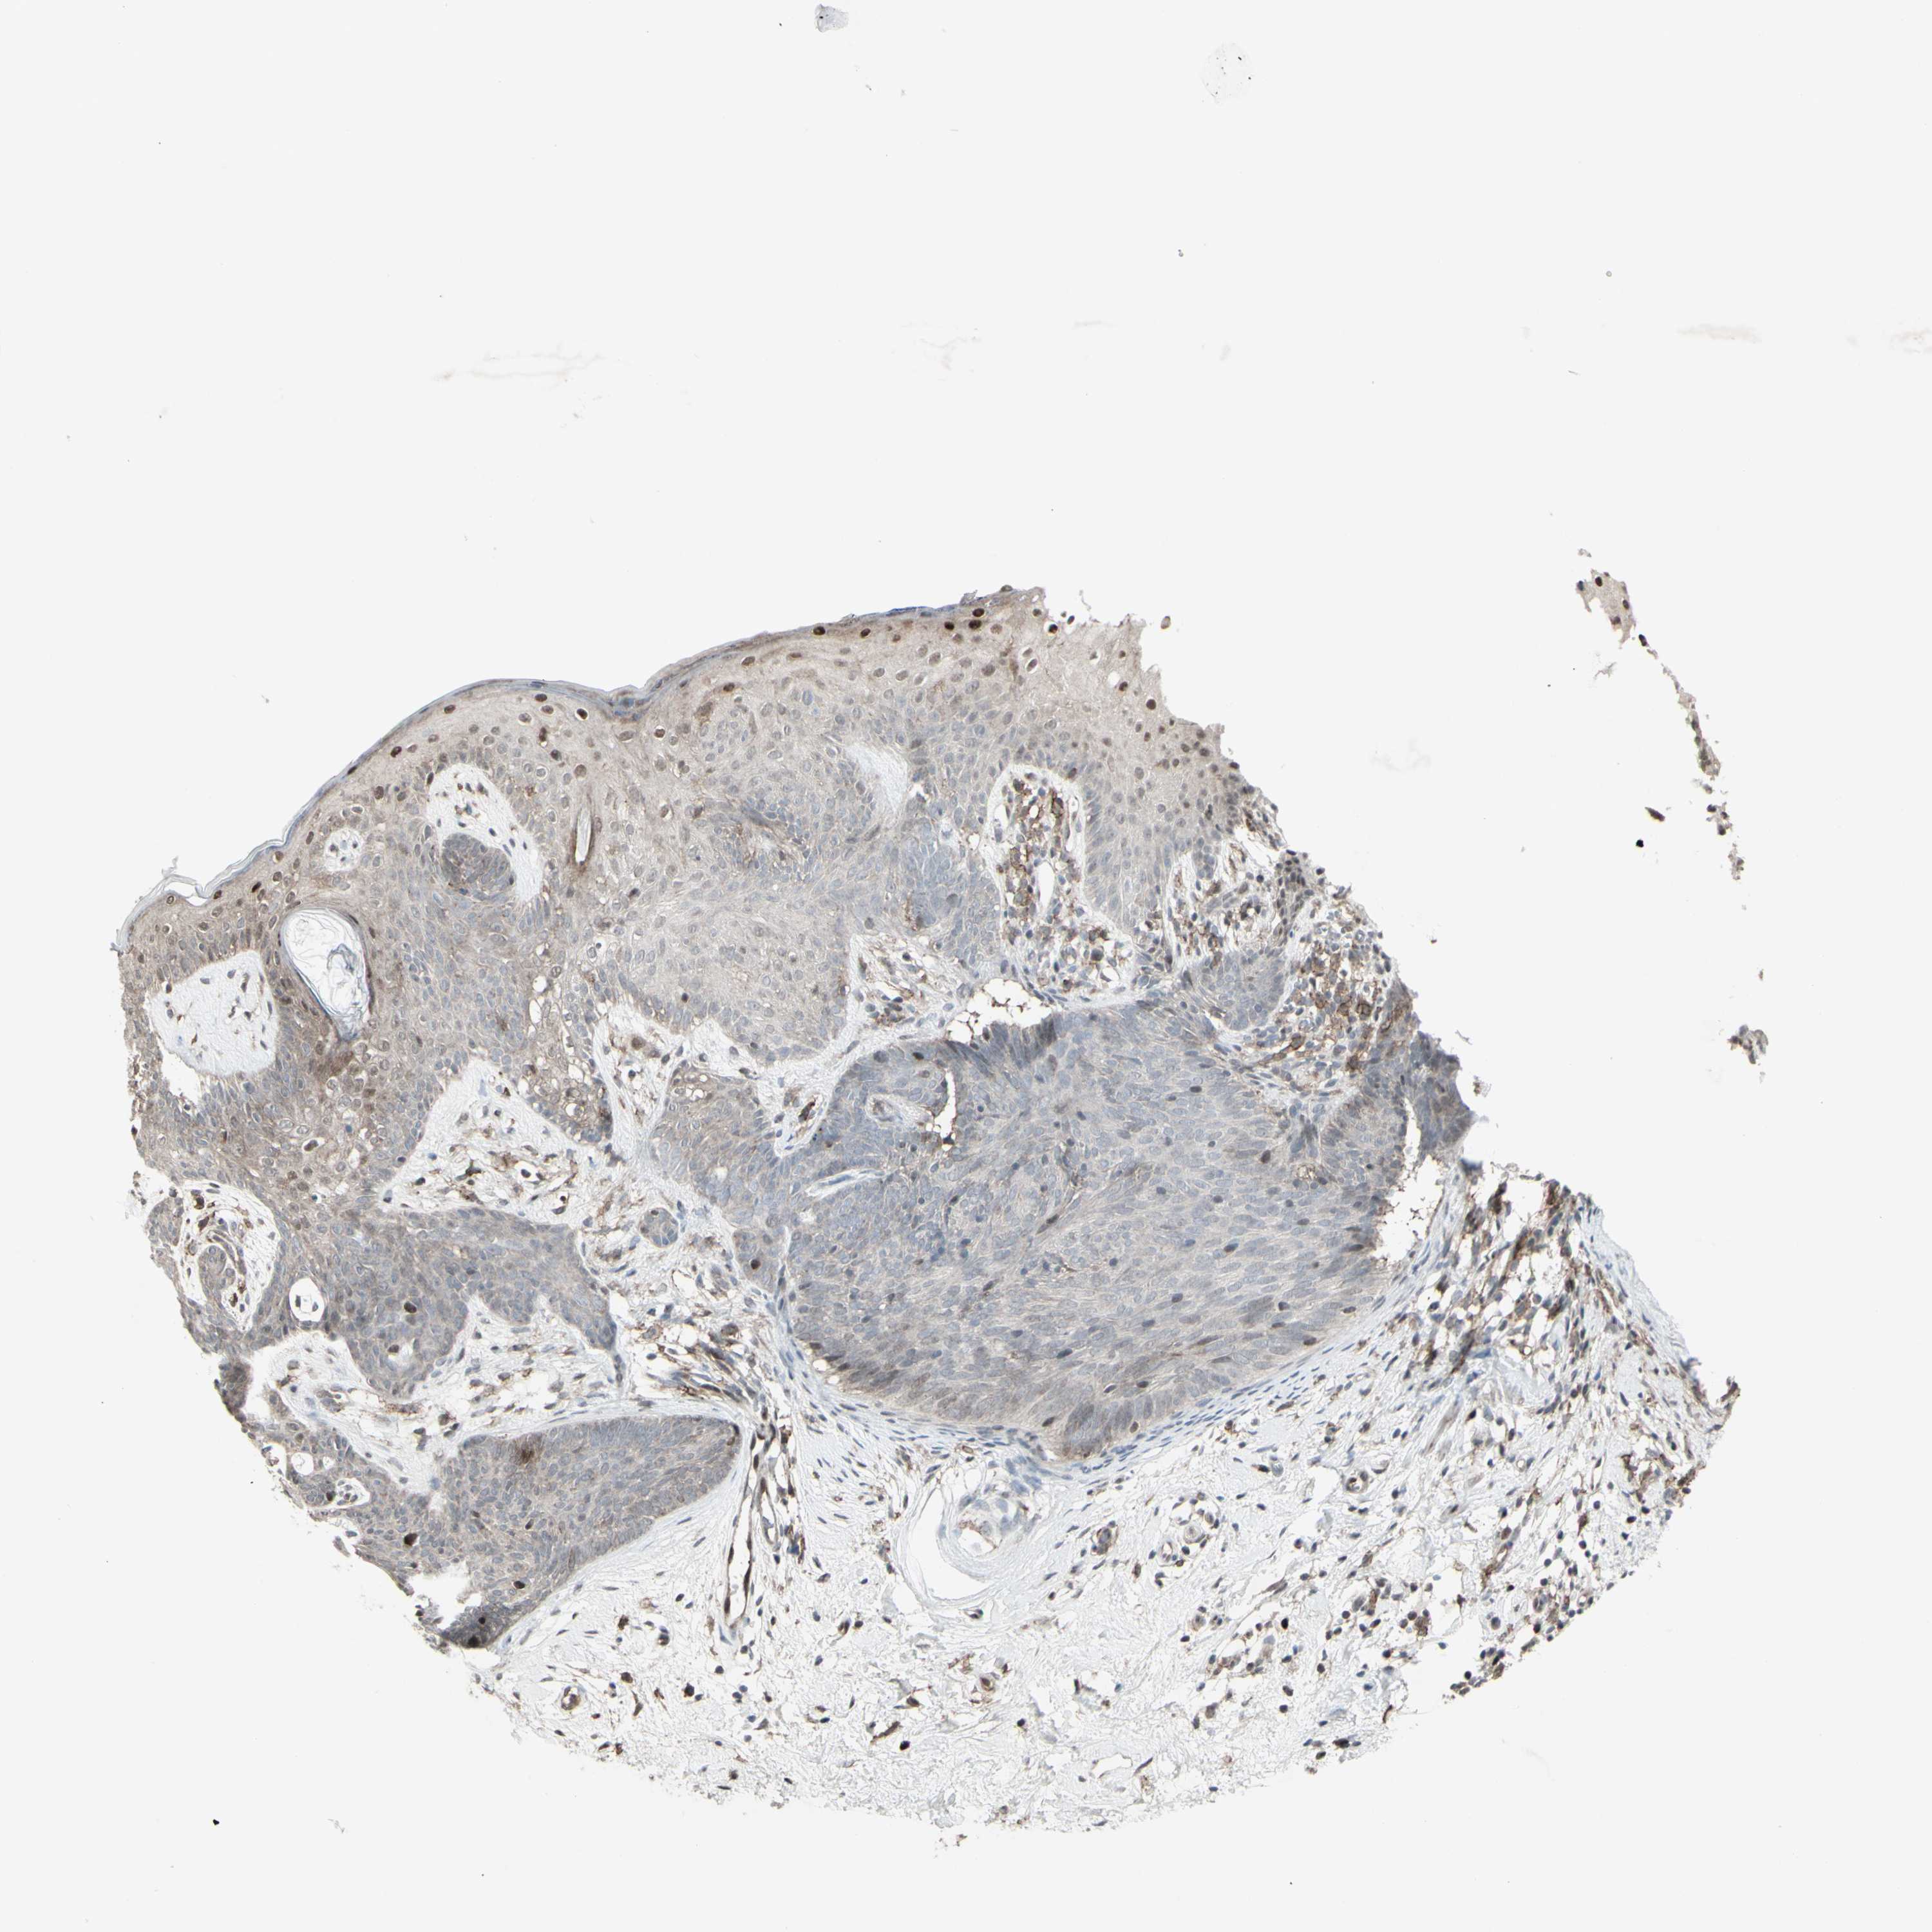

SKIN CANCER - Protein expressioni

A mouse-over function shows sample information and annotation data. Click on an image to view it in a full screen mode. Samples can be filtered based on level of antibody staining by selecting one or several of the following categories: high, medium, low and not detected. The assay and annotation is described here.

Each image is clickable and will lead to virtual microscopy that enables deeper exploration of all samples and also displays staining intensity scores, fraction scores and subcellular localization as well as patient and tissue information for each sample.

Antibody CAB079996

Squamous cell carcinoma, NOS